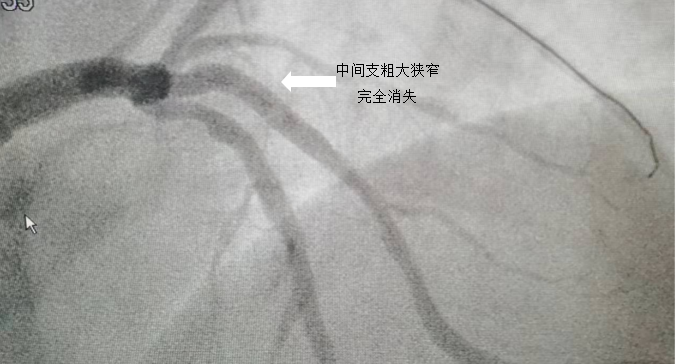

2.唐某,42岁,危险因素包括高血压、糖尿病和长期抽烟。本次因反复劳力后胸闷来我院,近期胸痛发作频繁。冠脉CT提示三支血管病变(左前降支、左回旋支重度狭窄)。

病例2

中间支的近端重度狭窄,呈次全闭塞

粗大中间支在植入支架后,狭窄完全消失